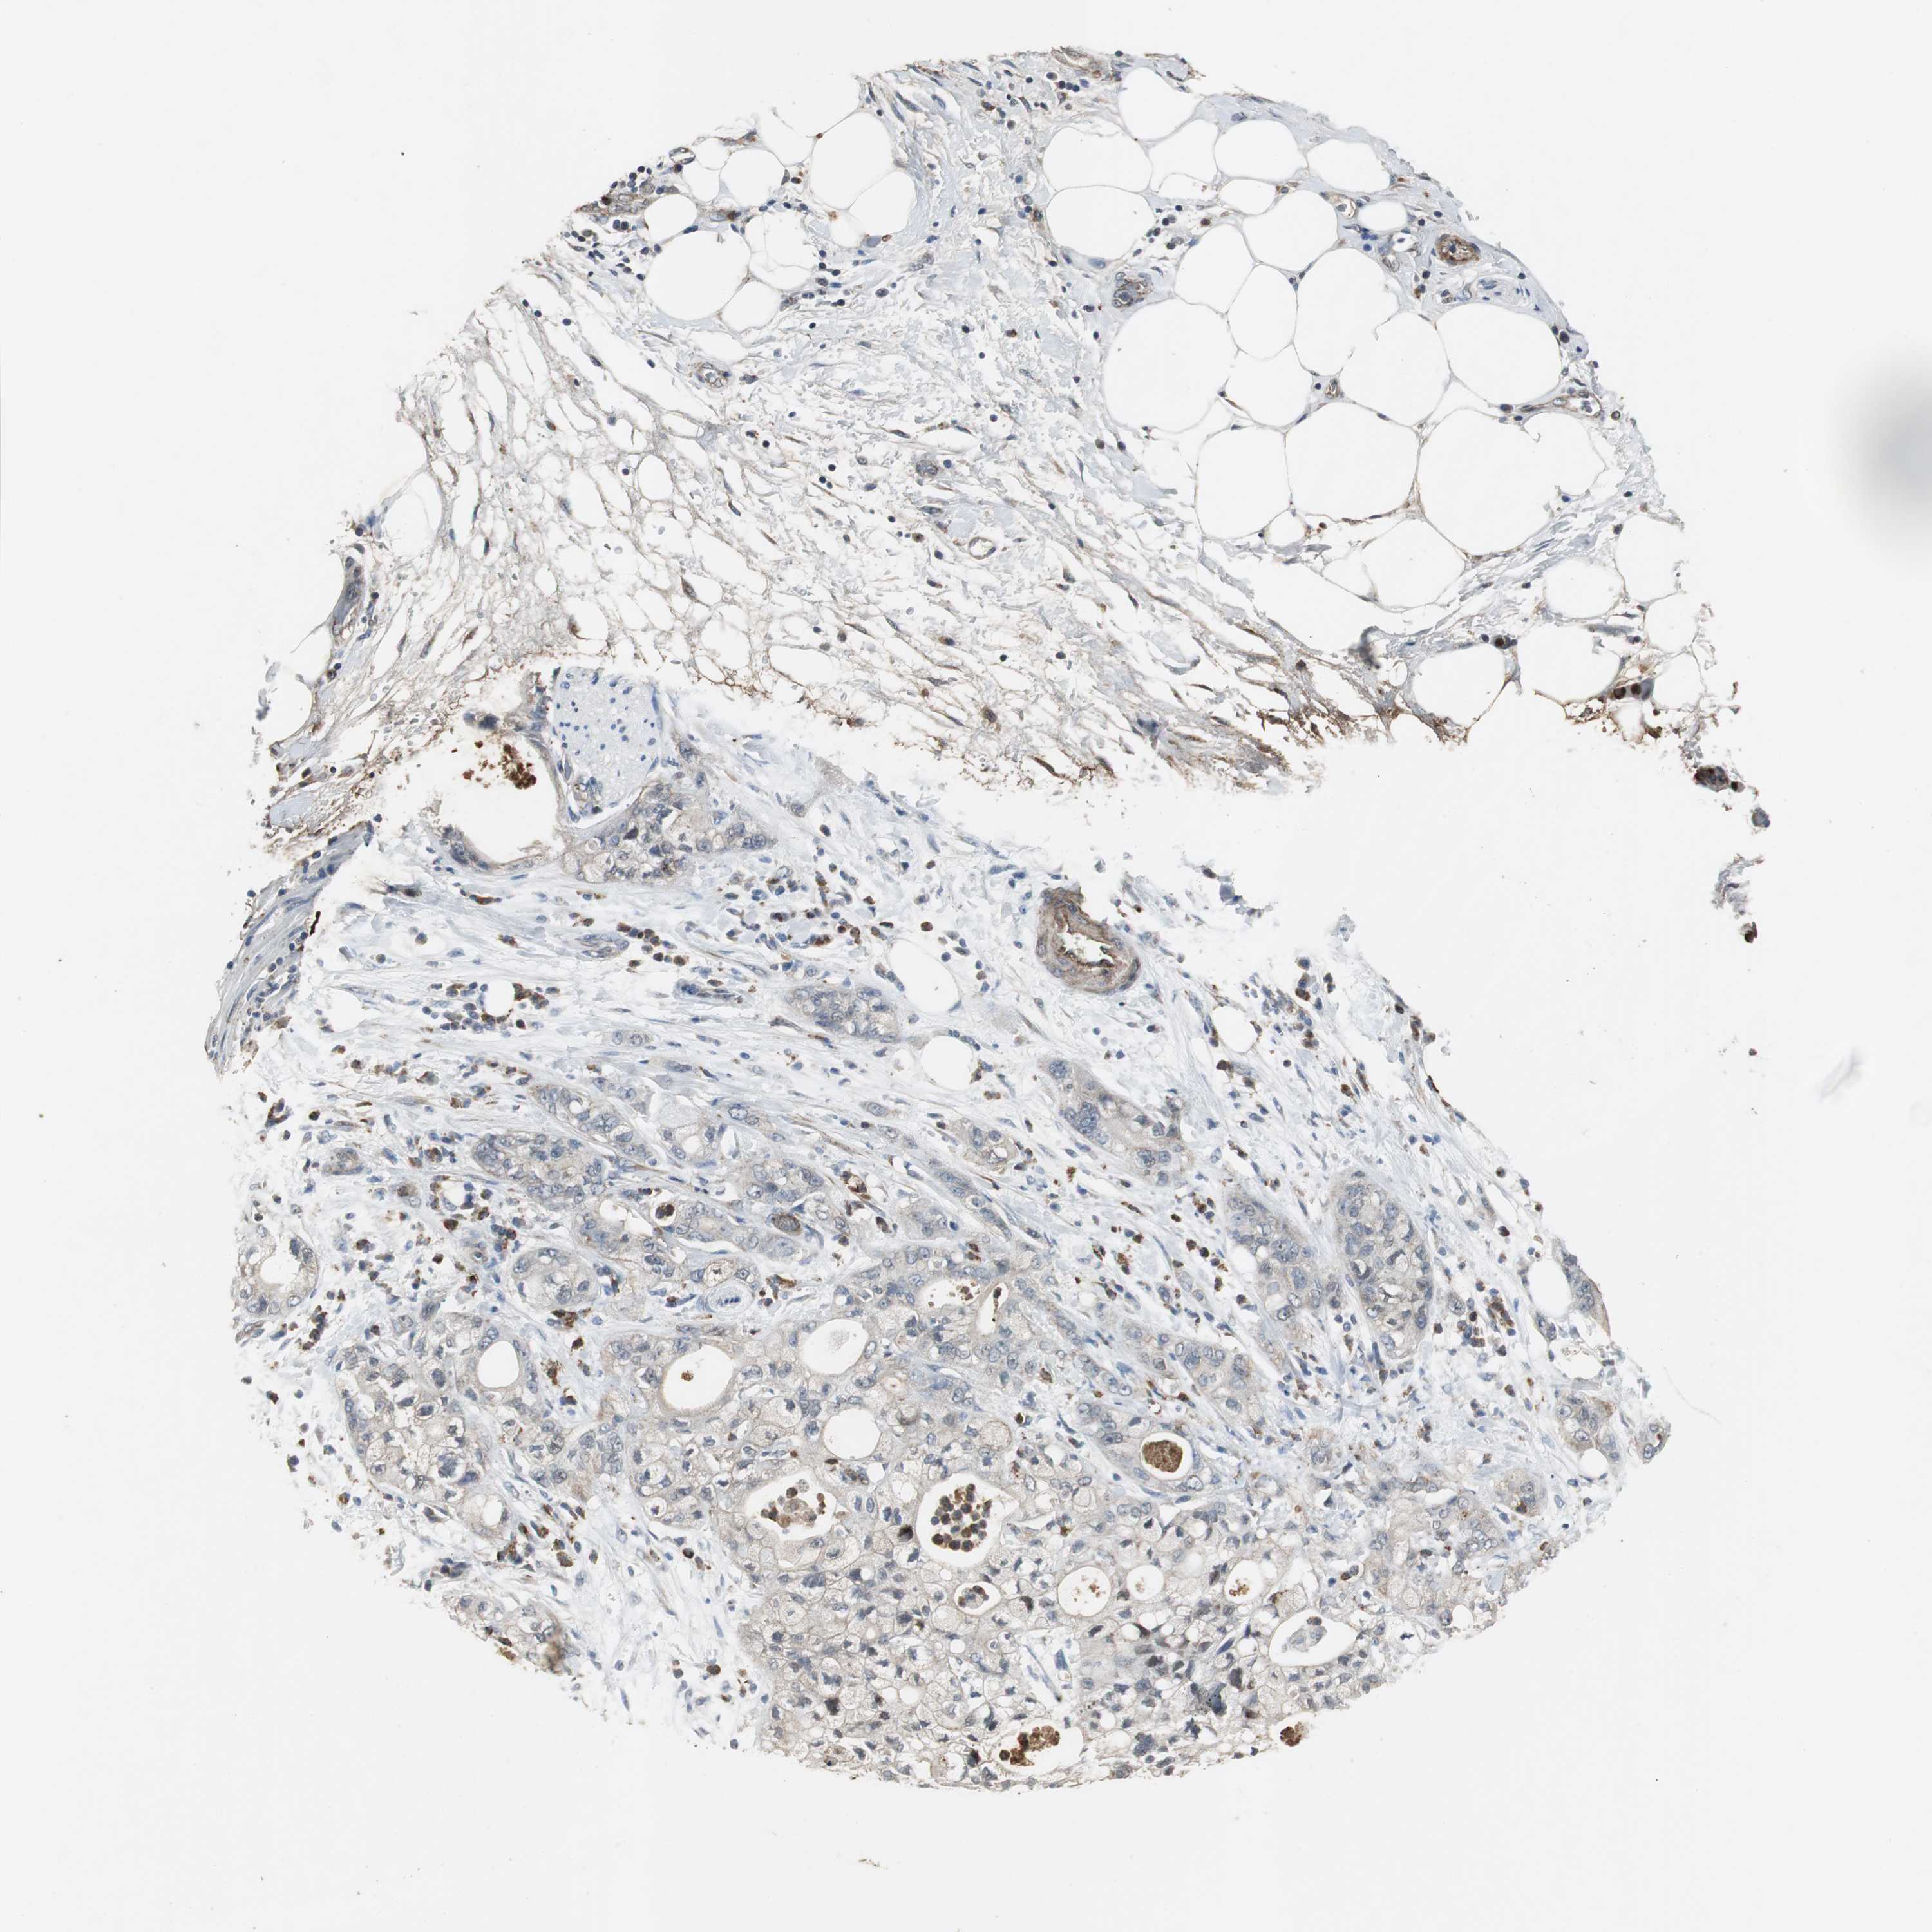

PANCREATIC CANCER - Protein expressioni

A mouse-over function shows sample information and annotation data. Click on an image to view it in a full screen mode. Samples can be filtered based on level of antibody staining by selecting one or several of the following categories: high, medium, low and not detected. The assay and annotation is described here.

Note that samples used for immunohistochemistry by the Human Protein Atlas do not correspond to samples in the TCGA dataset.

Antibody stainingi

Antibody staining in the annotated cell types in the current human tissue is reported as not detected, low, medium, or high, based on conventional immunohistochemistry profiling in selected tissues. This score is based on the combination of the staining intensity and fraction of stained cells.

Each image is clickable and will lead to virtual microscopy that enables deeper exploration of all samples and also displays staining intensity scores, fraction scores and subcellular localization as well as patient and tissue information for each sample.

Antibody HPA006514

Staining

High

Medium

Low

Not detected

Intensity

Strong

Moderate

Weak

Negative

Quantity

>75%

75%-25%

<25%

None

Location

Nuclear

Cytoplasmic/membranous

Cytoplasmic/membranous,nuclear

Adenocarcinoma, NOS

Adenocarcinoma, metastatic, NOS